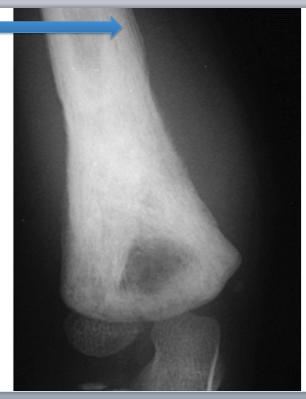

What is this?

Osteosarcoma

Cells in osteoid irregular, tripolar mitosis